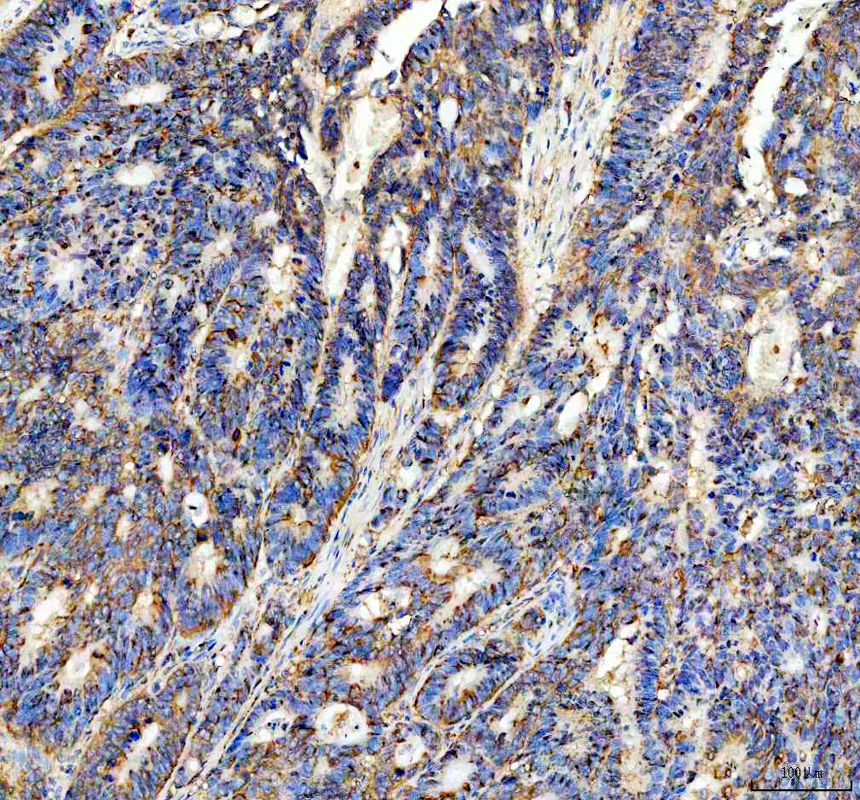

IHC analysis of PSEN1 using anti-PSEN1 antibody (BM5520) .

PSEN1 was detected in a paraffin-embedded section of human stomach cancer tissue. The tissue section was incubated with rabbit anti-PSEN1 Antibody (BM5520) at a dilution of 1:200 and developed using HRP Conjugated Rabbit IgG Super Vision Assay Kit (Catalog # SV0002) with DAB (Catalog # AR1027) as the chromogen.